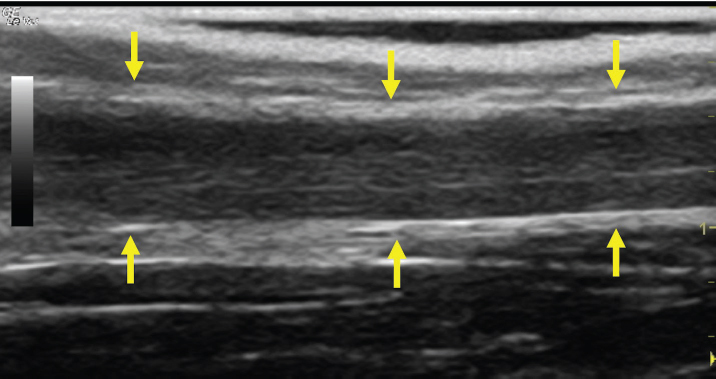

The left jugular vein appeared as an anechoic tubular structure which collapsed under the probe pressure, the color Doppler examination revealed normal blood flow within the vessel (Fig. 3). Bi-dimensional ultrasonography of the right jugular vein showed a heterogeneous, non-cavitating, hypoechoic structure occluding a narrowed right jugular vein for about 30 cm of length localized in the proximal and mid-portion of the neck compatible with a thrombus (Fig. 4). The color Doppler examination showed blood flow through the lateral portions of the thrombus in the cranial and mid-portions of the right jugular vein (Fig. 5). Cranially to the thrombus, a marked distension of the maxillary and linguofacial veins was evident, with a turbulent and echogenic flow; the latter was compatible with blood stasis near the thrombus (Fig. 6). Caudally to the thrombus, the right jugular vein presented reduced diameter, thickened walls, and normal blood flow (Fig. 7). The cranial part of the thrombus originated from a heterogeneous scare tissue, localized at the level of the right mandibular angle (Fig. 8). After injection of the first saline contrast bolus in a right facial vein, no microbubbles appeared in the right jugular vein, caudally to the thrombus, proving the presence of a complete right jugular vein occlusion. On the contrary, after injection of the second bolus, microbubbles were visualized in the left jugular vein as small, intense, echo signals within the vein lumen, demonstrating the presence of collateral circulation that drained the blood from the right facial veins to the left jugular vein (Fig. 9). Venography results confirmed the complete occlusion of the right jugular vein and the presence of submandibular venous collaterals that connected the right facial veins with the left jugular vein (Figs. 10 and 11). Based on the previous results, the diagnosis of JVT with complete occlusion of the vessel lumen was confirmed. The horse’s owner refused any proposed medical or surgical therapy.

Fig. 7. Bi-dimensional ultrasonographic image of the right jugular vein, caudally to the thrombus, in longitudinal section (arrows). No microbubbles appeared caudally to the thrombus, following injection of the first saline contrast bolus.